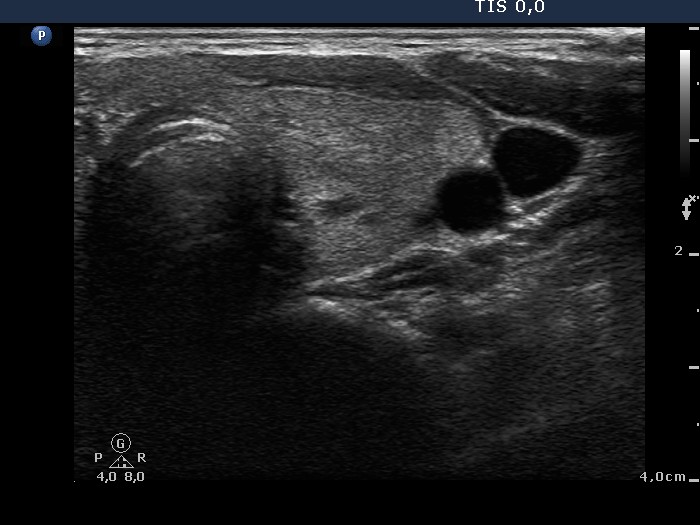

Follow-up investigation 36 months after first visit (ultrasonographic picture 4)

Patient on daily 10 mg methimazole therapy in euthyroid state

Left lobe, transverse view. Small minimally hypoechogenic areas are found within an echonormal background.